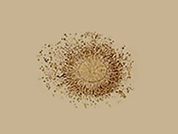

난자는 구형의 모양을 가지며 크기는 정자의 약 10배로써 0.1mm 정도입니다. 세포질의 일부는 수정 후 분열과 개체 발생에 필요한 에너지원이 되고 일부는 개체의 구성물질이 됩니다. 난자는 난소에서 생성됩니다. 가임기 여성의 난소에는 반짝거리는 투명한 작은 난포가 수없이 형성되어 있습니다.